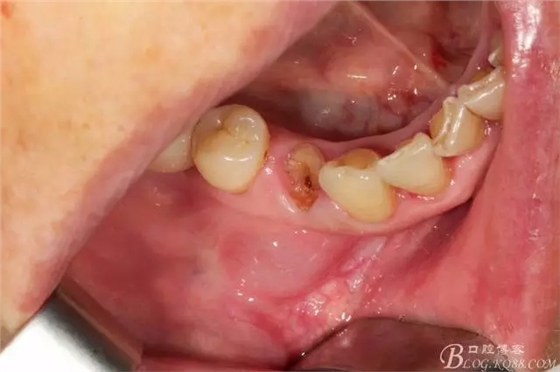

44號(hào)牙位術(shù)前照片

拔牙 當(dāng)然這種手術(shù)我必須不翻瓣零翻瓣